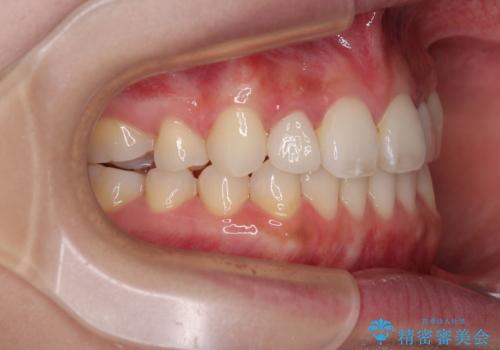

飛び出した前歯 インビザラインを用いた抜歯矯正治療

- 前方に飛び出した前歯を気にして来院された患者様です。

上下前歯同士の距離が離れているため、上顎左右第一小臼歯2本を抜歯することで前突を改善することとしました。

しかしながら、左右ともに側切歯が矮小歯であるため、矯正治療で矮小歯前後にスペースを作り、矯正治療後にオールセラミッククラウンにて補綴治療を行うこととしました。